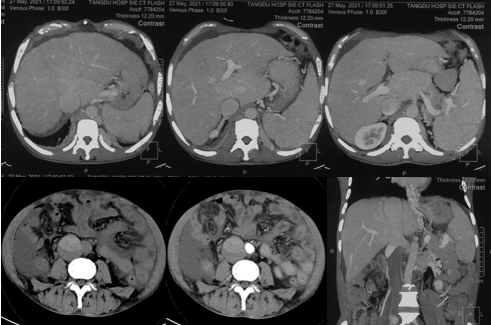

6月20日,患者及家屬懷揣著忐忑的心情來(lái)到西安國(guó)際醫(yī)學(xué)中心醫(yī)院找到韓國(guó)宏教授,韓教授詢問病情后閱患者外院CT片,明確診斷布加綜合征,同時(shí)發(fā)現(xiàn)了一個(gè)新的問題,在詢問病史時(shí)了解到患者近一周雙下肢乏力伴腫脹明顯加重,遂立即安排了急診CT,證實(shí)下腔靜脈內(nèi)急性血栓形成!

6月22日,在韓國(guó)宏教授的帶領(lǐng)下,患者于消化介入診療中心行下腔靜脈開通術(shù)。術(shù)中可見:下腔靜脈全段擴(kuò)張,膜性閉塞,腎靜脈平面以下可見血栓形成并伴有粗大的側(cè)枝靜脈,遂對(duì)狹窄段球囊擴(kuò)張并植入支架,術(shù)后下腔靜脈血流通暢,側(cè)枝消失。術(shù)后第2天,患者腹壁靜脈曲張幾乎消失不見,走路也輕快了許多。明明只是薄薄的一層膜,為什么開通起來(lái)這么難?韓教授指出,盡管布加綜合征介入開通技術(shù)已使創(chuàng)傷降到了最低,但受到患者個(gè)體差異及醫(yī)療水平參差不齊的限制,仍有可能出現(xiàn)嚴(yán)重的并發(fā)癥,主要包括:心包積血、縱隔血腫、心包填塞甚至下腔靜脈撕裂引起的大出血等。而其發(fā)生率與術(shù)者的操作熟練程度及經(jīng)驗(yàn)有很大的關(guān)系。